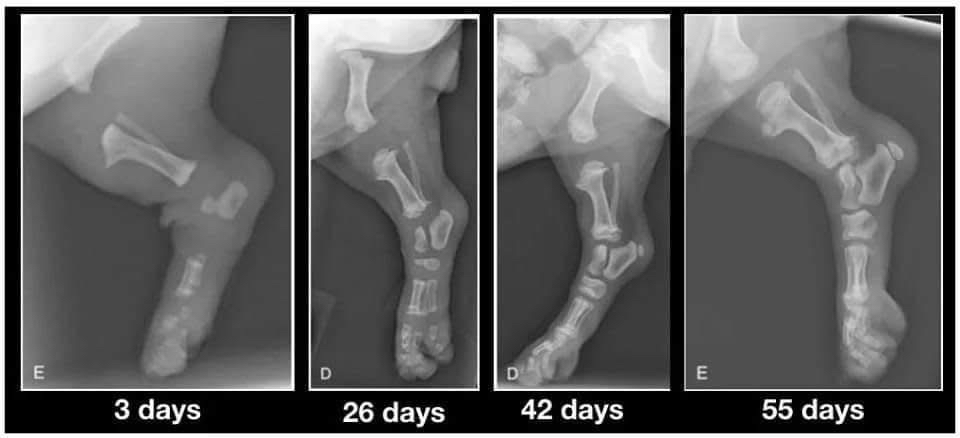

Lorsque vous accueillez enfin vos chiots de 9 semaines, veuillez garder cette image à l'esprit. Leurs os ne se touchent même pas encore. Ils marchent si joliment avec de grosses pattes souples et des mouvements bancals parce que leurs articulations sont entièrement constituées de cartilages, de muscles, de tendons et de ligaments recouverts de peau. Rien n'est encore bien ajusté ou n'a encore de véritable prise.

Lorsque vous les faites courir de manière excessive ou que vous ne limitez pas leur exercice pour les empêcher d'en faire trop pendant cette période, vous ne leur donnez pas la chance de grandir correctement. Chaque grand saut ou course bondissante et excitée provoque des impacts entre les os. En quantités raisonnables, ce n'est pas problématique et c'est une usure normale qui s’opèrera.

Mais lorsque vous laissez le chiot sauter du canapé ou du lit, l’emmenez faire de longues promenades, vous endommagez cette articulation en formation. Lorsque vous laissez le chiot se déplacer sur des carreaux glissants, vous endommagez l'articulation.

Vous n'avez la chance de les faire grandir qu'une seule fois. Un corps bien construit est quelque chose qui vient d'un excellent élevage et d'une bonne éducation. LES DEUX, pas seulement un.

Une fois adulte, vous aurez le reste de votre vie à passer à jouer et à vous engager dans des exercices à fort impact. Alors gardez-le au calme tant qu’il est encore petit et offrez-lui le cadeau qui ne peut être offert qu'une seule fois.